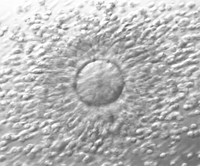

Oocyte donation (egg donation) is a treatment that involves using eggs from a donor. The next step entails either a synchronised treatment, meaning the donor and recipient are medicated in parallel to match the timing of egg retrieval and embryo transfer, or the use of vitrified donated eggs, which obviates the need for simultaneous treatment.

After fertilisation, the embryos are monitored in the laboratory. They are supervised by biologists and monitored to ensure their proper development in the initial stages. They are kept in incubators at a constant temperature in culture media suitable for their proper development.

Between two and three days later, they are evaluated and selected for transfer to the patient and/or vitrification. Not all of them develop correctly, so some will interrupt their development and be discarded for transfer.

In certain situations, it is considered suitable to cultivate embryos for a longer period, reaching the 'blastocyst' stage, a more mature form, before their transfer on the fifth or sixth day of development.